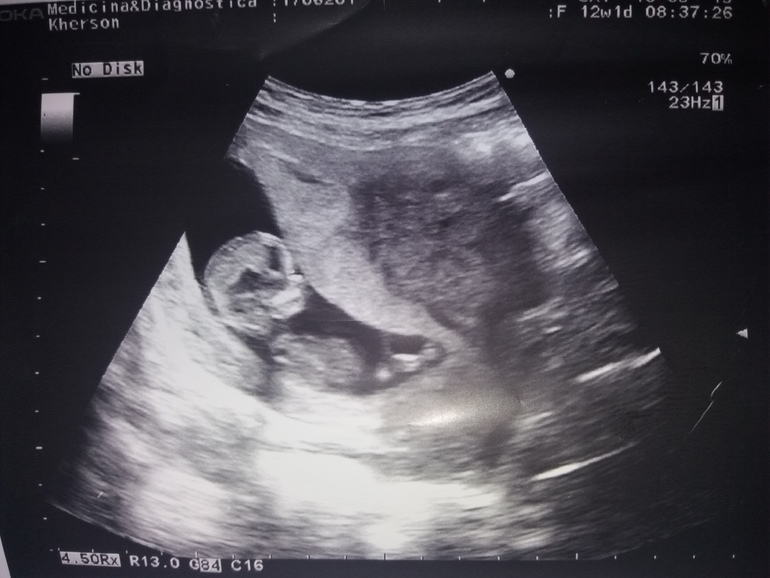

Пол малыша

Девчонки подскажите видно вам ли половой бугорок? у других вроде замечаю , а вот у себе нет ,фото по узи срок 10.2 , по М больше было , сегодня 12.2 после 1 скрининга сказали больше на мальчика .Есть фото за 12 недель но там я вообще не вижу, тут хоть что то вроде видно))) Если видно вам как думаете девочка или мальчик ? Знаю что предположения насчет пола не очень на маленьком сроке, но все же очень хочу уже своей ляльке делать прическе и нарядами баловать😏

первое фото 10.2

второе 12.2 (нед)(нед)